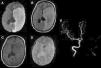

Uno de los efectos adversos más frecuentes en nuestra serie fue el PRES, el cual afectó al 20% (n=3) del total de los pacientes. Un caso fue producido por pazopanib, el cual se halla reportado en el prospecto, y los otros 2 casos fueron secundarios al uso de IgEV, los cuales no se hallaban mencionados en su prospecto. En todos los casos, el efecto adverso revirtió tras la suspensión de los fármacos (fig. 3).

PRES secundario a pazopanib (arriba) y a IgEV (abajo). (A y B) RM secuencia FLAIR que muestra múltiples imágenes hiperintensas bilaterales, relativamente simétricas. (C) RM en secuencia FLAIR que evidencia lesiones hiperintensas bilaterales a nivel occipitotemporales. (D) RM control al mes de suspensión de IgEV evidenciando resolución de lesiones previas.

IgEV: inmunoglobulina humana; PRES: síndrome de encefalopatía posterior reversible; RM: resonancia magnética.